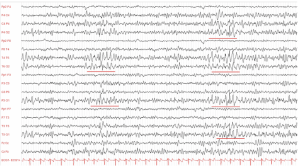

Take our EEG Test Questions!

Are you prepping for your EEG boards? 🧠📚

Do you just like engaging in posts about the NDT field? ✔

Engage with our community and enhance your knowledge in the neurodiagnostic field with our EEG Fun Facts. Each fact comes with a question and multiple choice answer to choose from to test your knowledge!